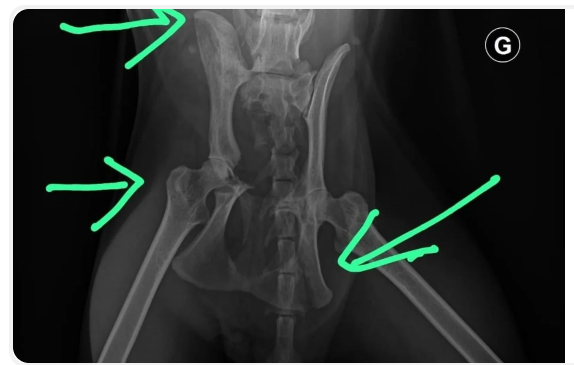

Certaines prises en charge de chats dépassent malheureusement les soins habituels. Dans certains cas, les animaux arrivent dans un état de santé extrêmement grave ou nécessitent des traitements longs, spécialisés et coûteux (chirurgies lourdes, hospitalisations, soins vétérinaires intensifs, etc.).